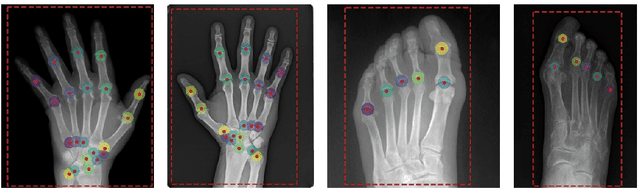

Abstract:Recent advancements in computer vision promise to automate medical image analysis. Rheumatoid arthritis is an autoimmune disease that would profit from computer-based diagnosis, as there are no direct markers known, and doctors have to rely on manual inspection of X-ray images. In this work, we present a multi-task deep learning model that simultaneously learns to localize joints on X-ray images and diagnose two kinds of joint damage: narrowing and erosion. Additionally, we propose a modification of label smoothing, which combines classification and regression cues into a single loss and achieves 5% relative error reduction compared to standard loss functions. Our final model obtained 4th place in joint space narrowing and 5th place in joint erosion in the global RA2 DREAM challenge.